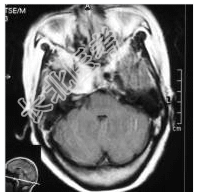

- [材料题] 患者,女性,59岁,因复视、右面瘫及蚁行感半年,间有头疼,无呕吐入院。体检:神清,右外展不全,复视,右面部皮肤感觉尚好,伸舌居中,右指鼻试验(-),四肢(-)。做头颅MRI检查。

- 简答题1、请问诊断是什么?

- 简答题2、诊断依据是什么?

- 简答题3、鉴别诊断有哪些?